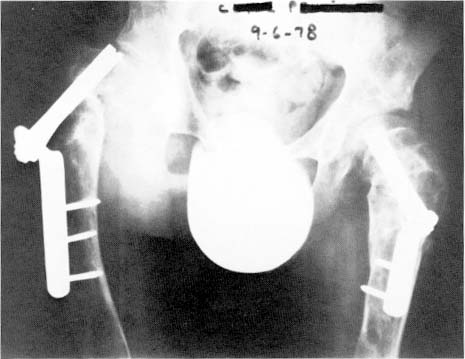

Fig 3-A: Case 3 - Radiograph made at the time of presentation showing thesecond set of Smith-Petersen nails with the right nail cutting out of the femoralhead.